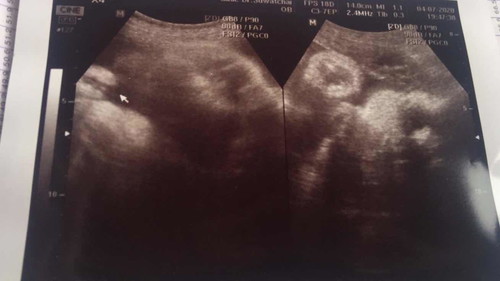

37w6d หญิงแน่นอนจ้า

ปวดหน่วงช่วงล่างมาก ถีบเก่ง กำหนด23/7ไม่รู้จะออกมาก่อนไหม. ตอนนี้แม่อยากให้ออกมาแล้ว